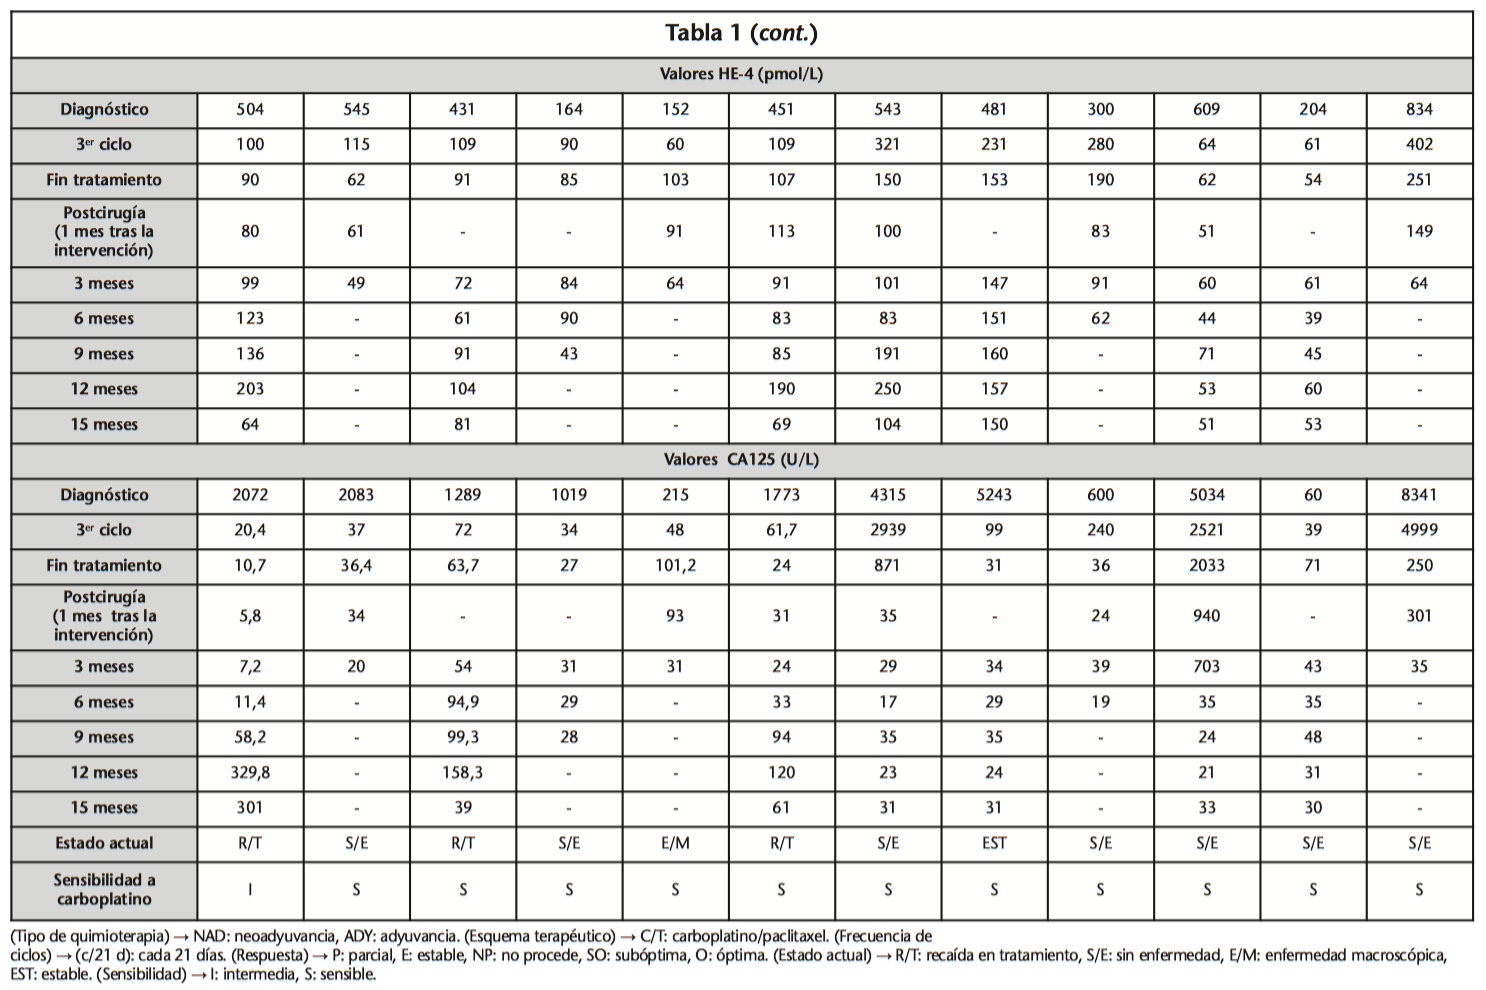

Cumplir Australia insalubre Comparación del comportamiento sérico de HE4 y CA125 como marcadores tumorales de cáncer epitelial ovárico. Análisis de doce casos clínicos - ILAPHAR | Revista de la OFIL

Pase para saber Psicológico pueblo Marcadores tumorales en el diagnóstico de cáncer epitelial de ovario: caso de estudio Tumor markers in the diagnosis of epit